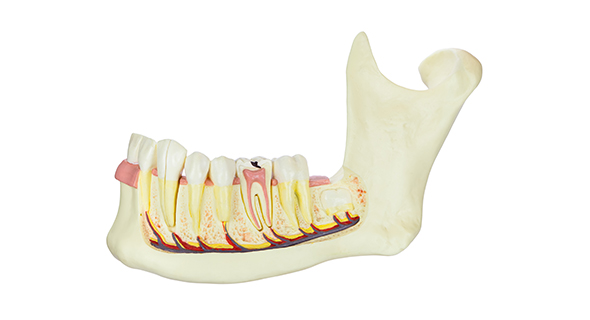

아래턱 뼈 안에는 “하치조신경“ 이라는 큰 신경이 좌우에 1개씩 있습니다.

아래 어금니 부위에 임플란트를 심을 때, 잇몸뼈와 하치조신경 사이의 거리를 정확히 계산해야 신경이 손상되는 것을 막을 수 있습니다.

윗니와 아랫니가 맞물리는 것을 “교합"이라고 합니다.

교합이 좋아야 잘 씹을 수 있고, 임플란트를 불편함 없이 오랫동안 사용할 수 있습니다.

이를 위해서는 임플란트 수술 시, 환자마다 잇몸뼈의 형태를 고려하여 최적의 치아 각도를 계산하여 진행해야 합니다.

또한 수술 후에 보철물의 치아 형태를 만들 때에도 최대한 자연 치아의 형태로 만드는 것이 중요합니다. -